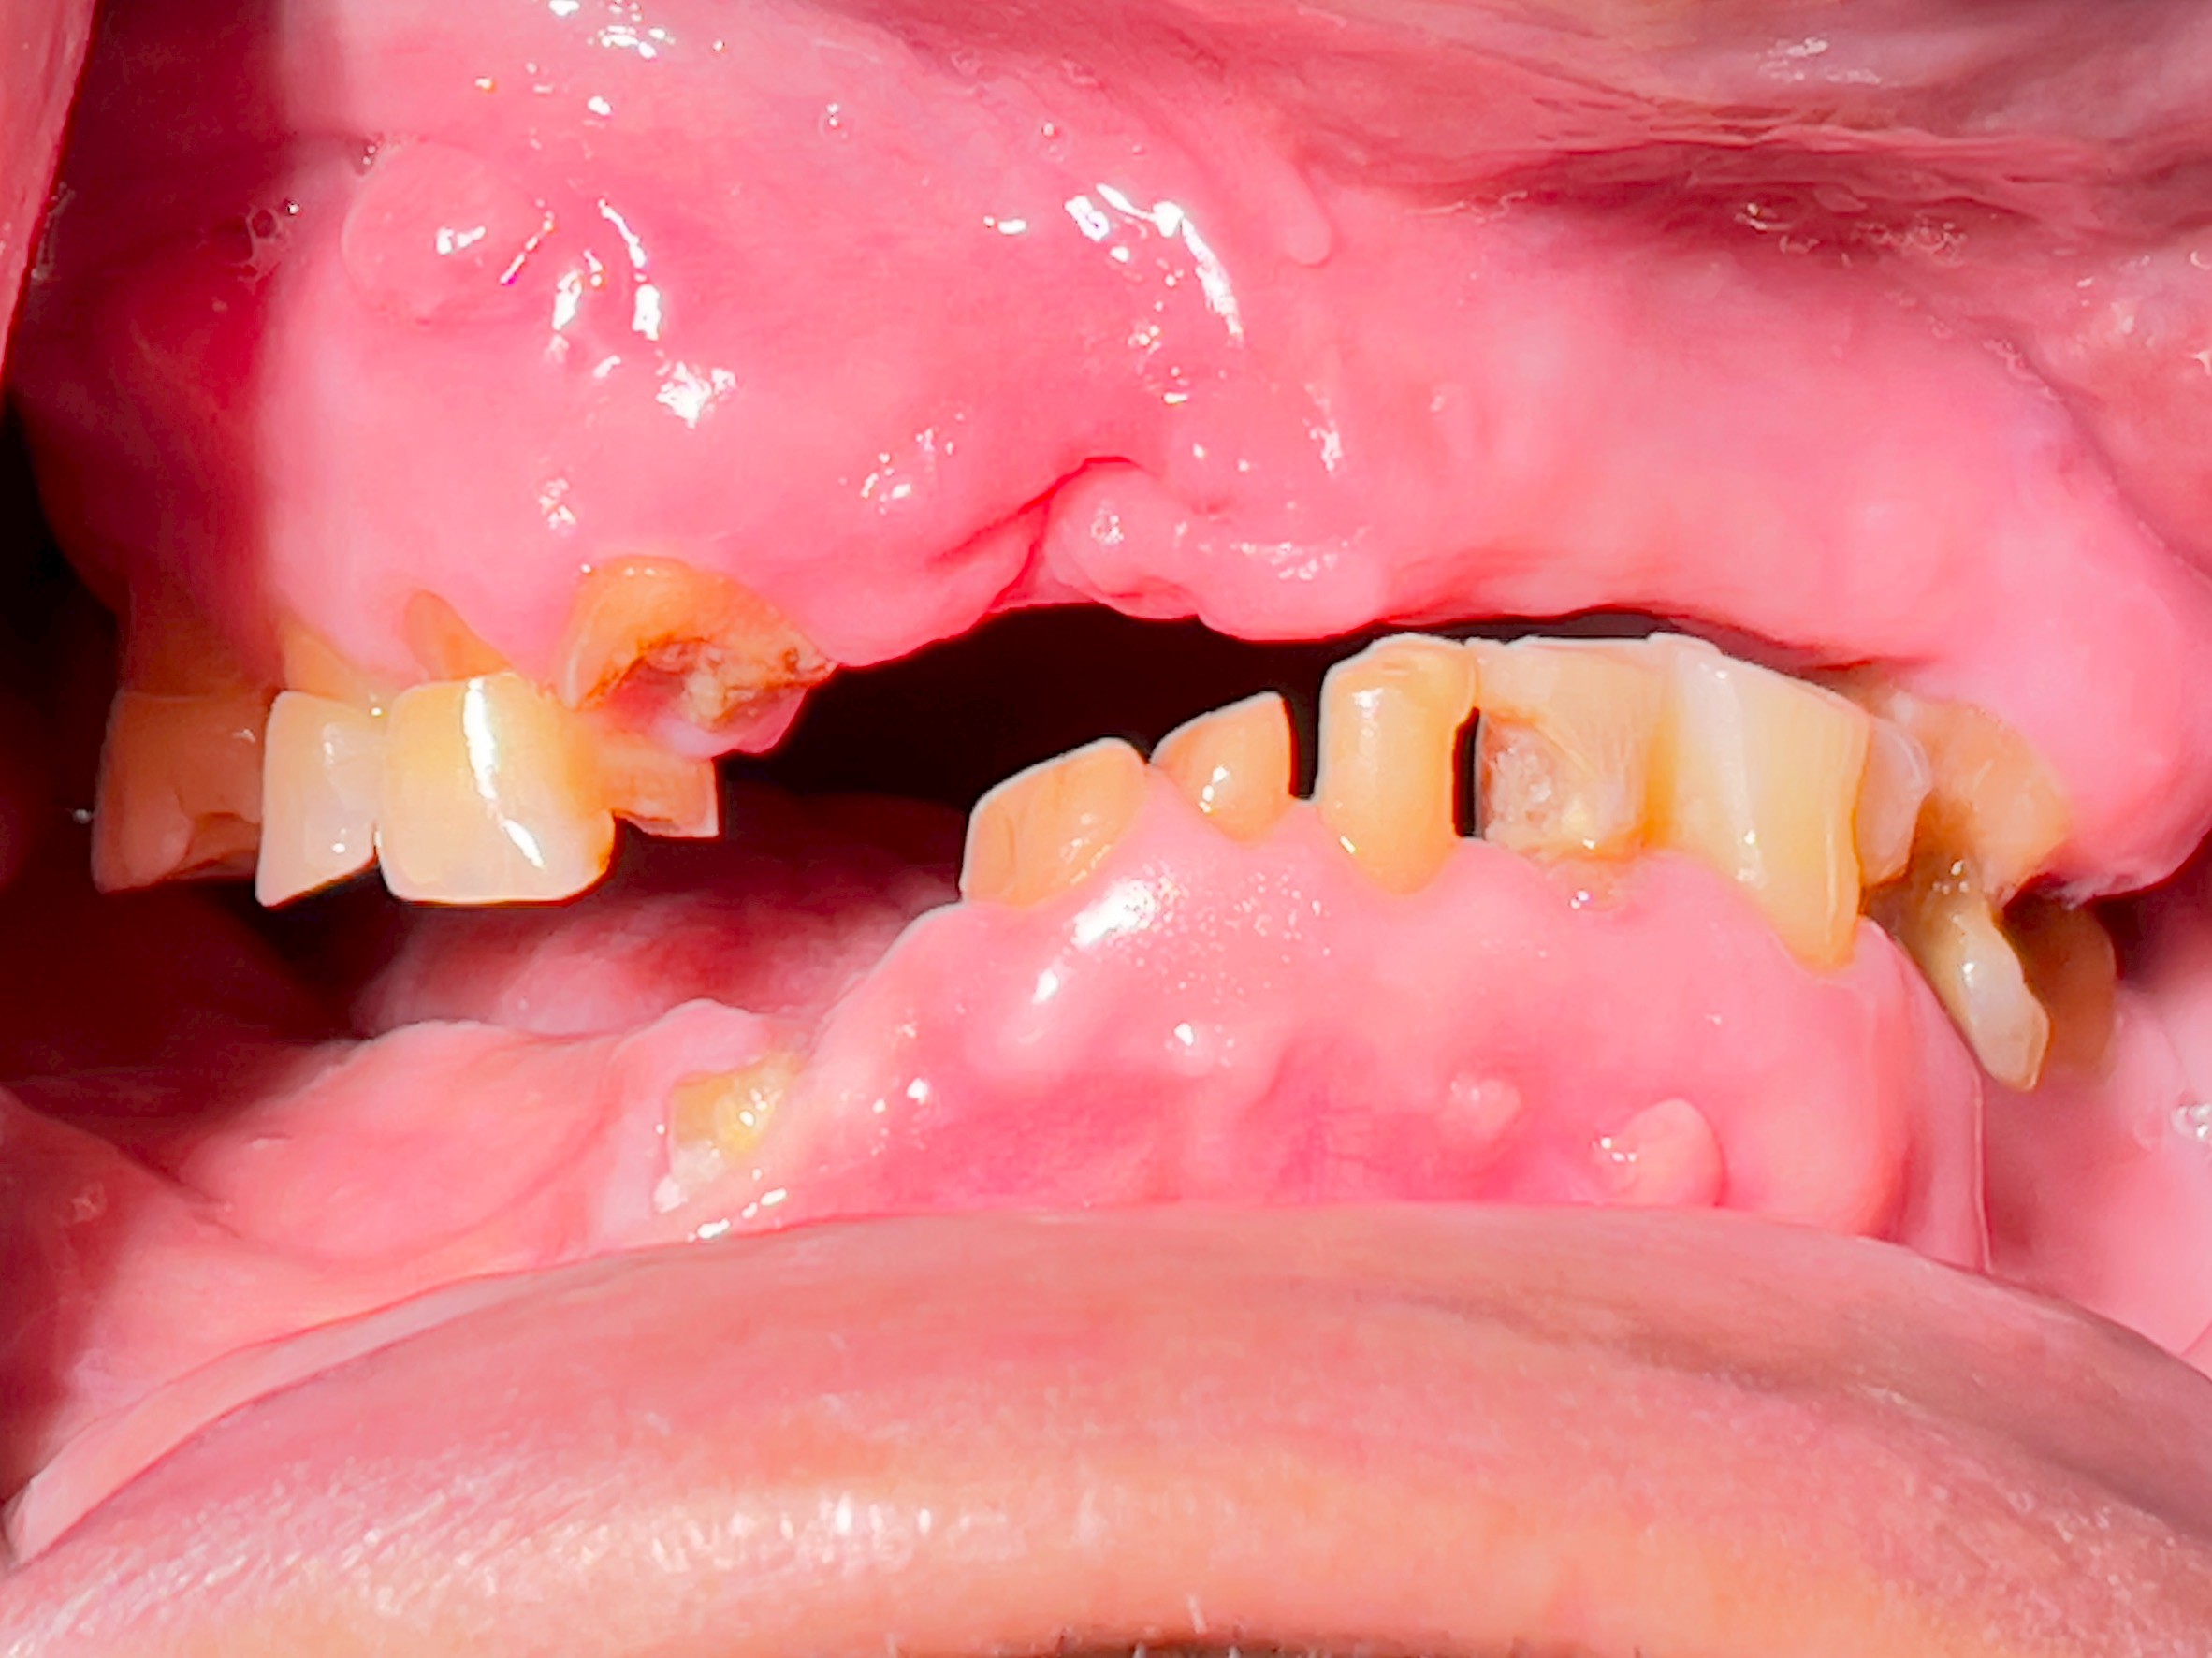

All-on-4 Implants Lower Jaw + Partial Denture Upper Jaw